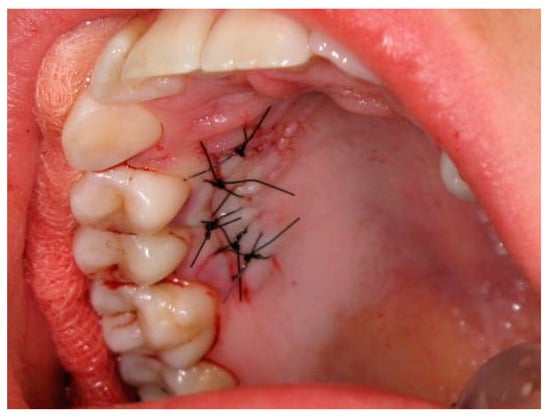

2.3. Surgical Procedures